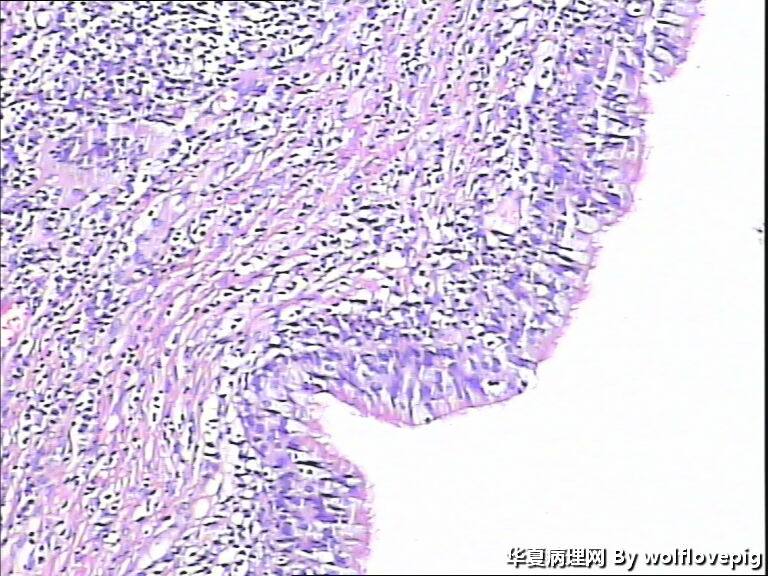

31y,阴蒂附近囊肿2.0*1.5cm

外阴最常见的囊肿是前庭大腺囊肿,囊肿一般衬以移行上皮,常伴有非角化性鳞状化生,也有的呈扁平或立方状,囊肿周边附近可以见到黏液腺体。

此例有点特殊,看到一些纤毛柱状上皮被覆,称为纤毛囊肿,属于前庭大腺囊肿的特殊改变。

前庭大腺囊肿位于外阴后半部,而此例位于阴蒂附近。

泌尿生殖窦起源的外阴囊肿(粘液性和纤毛囊肿)

1,多见于21-30及31-40的多产妇女,病变多位于外阴前庭。

2,组织学上,粘液性囊肿含有与宫颈内膜或阴道腺病一样的粘液性上皮内衬,少数情况下可出现鳞状上皮化生。也有报道有些病例出现纤毛细胞,可以与粘液上皮混合存在。